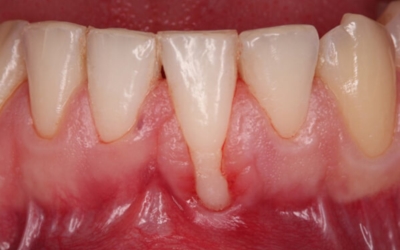

치은염에서 발전된 형태의 잇몸 염증 질환을 말합니다. 치은염이 잇몸 겉에 염증이 생긴 정도라면 치주염은 잇몸 겉에서 잇몸 뼈 주변까지 염증이 진행된 형태입니다. 따라서, 치은염보다 치료기간도 길어질 수밖에 없고 회복도 더딘 편입니다. 치주염은 치은염에서 발전된 형태이기 때문에 초기에는 양치질을 할 때 피가 나는 등의 치은염 증상을 겪게 돼요. 이후 치주염으로 발전한 초기에는 잇몸이 붓고 들뜬 느낌이 들며 붉어지고 건드렸을 때 출혈이 발생하게 돼요. 중기에는 잇몸이 내려가며 이 사이가 뜨기 시작해 치아가 조금씩 흔들리게 되고 말기에는 잇몸이 심하게 내려가 치아가 많이 흔들리게 돼요.